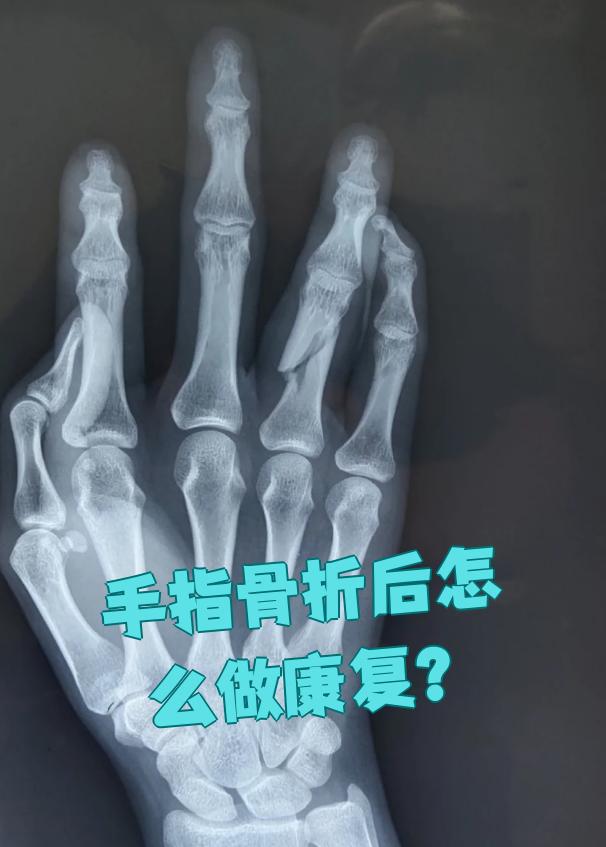

手骨折后的康复训练需结合病情所处时期进行,具体方法如下骨折早期12周此时骨折端尚未愈合,需避免剧烈活动以患肢肌肉的主动收缩与舒张为主,例如轻柔握拳后缓慢松开,或进行前臂肌肉的等长收缩训练此类训练可维持肌肉力量,同时促进局部血液循环,减轻肿胀和疼痛需注意动作幅度不宜过大。

手指骨折后的康复时间通常为8周至1年以上,具体时长取决于骨折类型治疗方式及个体恢复情况无移位的裂纹骨折若骨折未发生明显移位,通常采用外固定如夹板或支具治疗,固定46周后拆除外固定此时可开始手指屈伸功能锻炼,812周可基本恢复日常活动如抓握提物但精细动作如写字系。

手术治疗因骨折端不稳定等特殊情况采用,如克氏针固定,愈合时间相对保守治疗可能稍有不同,但总体也在4 8周左右,具体取决于手术和骨折恢复情况康复锻炼早期适当康复锻炼有助于促进血液循环,利于骨折愈合,固定后1 2周可进行手指轻微屈伸等活动,但要避免过度活动导致骨折端移位,坚持良好康复。

肌肉收缩训练在骨折愈合中期约46周,可借助橡皮筋弹性带或专业手部康复设备进行等长收缩练习例如,用橡皮筋缠绕手指进行抗阻屈曲或伸展,每组1015次,每日3组此类训练能增强手部肌肉力量,避免肌肉萎缩,同时促进血液循环,加速骨折愈合力量训练骨折愈合后期约68周后,需经X光确认骨痂。